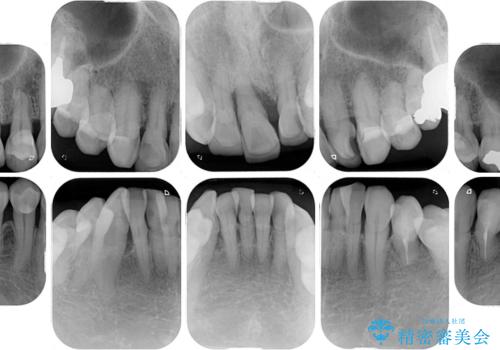

検査を行ったところ、前歯1本は周辺の骨が失われており、抜歯が必要でした。

上顎の奥歯は全体的に歯周ポケットが散見され出血が認められたため、歯周外科処置を行うこととしました。